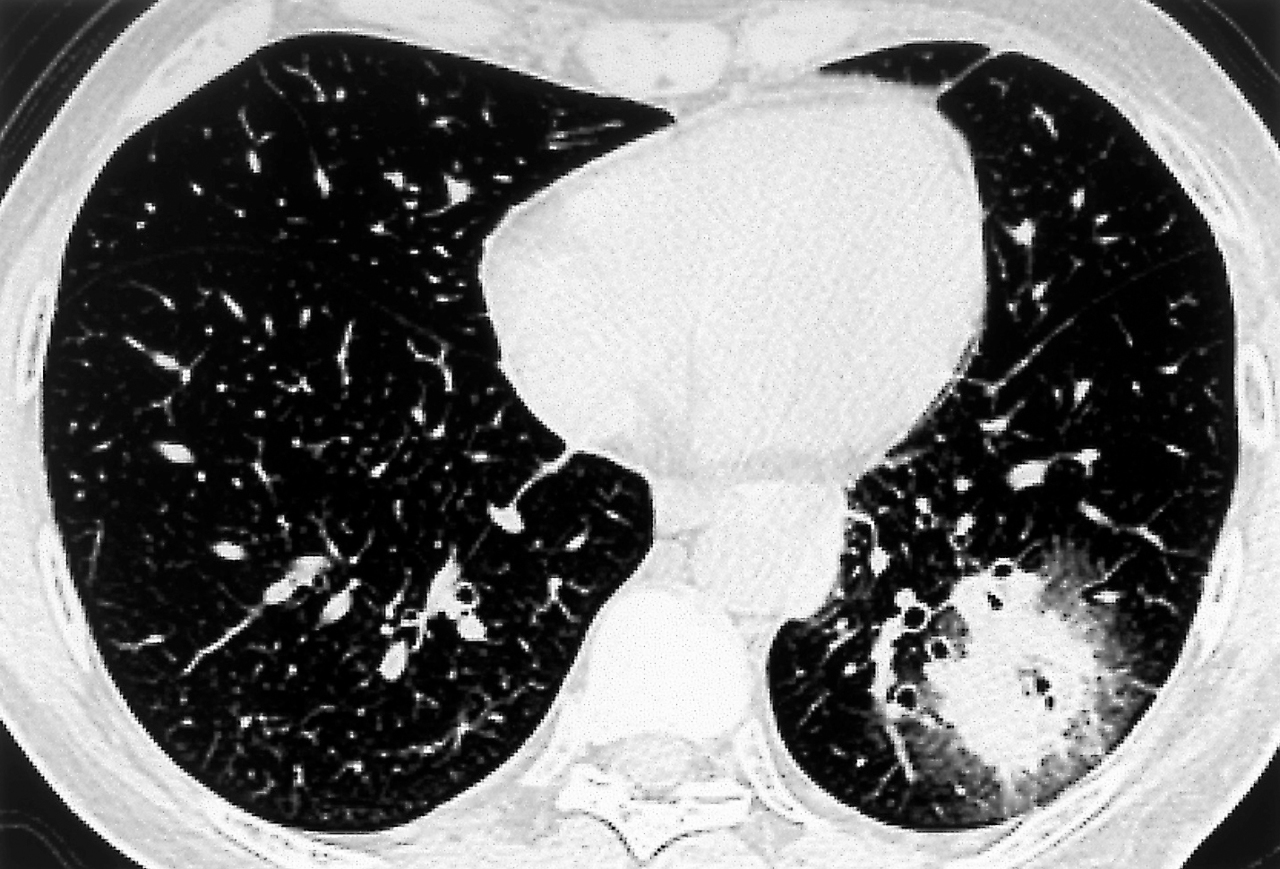

Quel est votre diagnostic ?

Il s'agit d'une aspergillose.